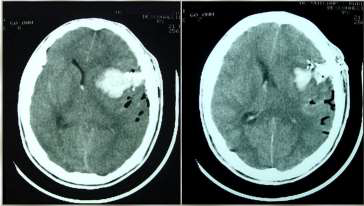

Paciente, 35 anos, sexo masculino, procedente de Recife-PE, é admitido em unidade de trauma, com história de agressão física por arma de fogo há 30 min. Veio trazido por policiais e sem profissional de saúde. Estava hipocorado, hipotérmico e possuía múltiplos orifícios de entrada de projétil de arma de fogo (PAF) em tórax, entrada e saída em região cervical e entrada em zigoma esquerdo. Apresentou parada cardiorrespiratória (PCR), revertida após 03 ciclos de reanimação cardiopulmonar, incluindo entubação orotraqueal sem sedação, expansão volêmica e drenagem torácica bilateral. Logo em seguida, após melhora hemodinâmica, não tinha abertura ocular e não tinha resposta motora, e pupilas estavam médio-fixas. De exame de imagem, fez apenas tomografia computadorizada (TC) de crânio.